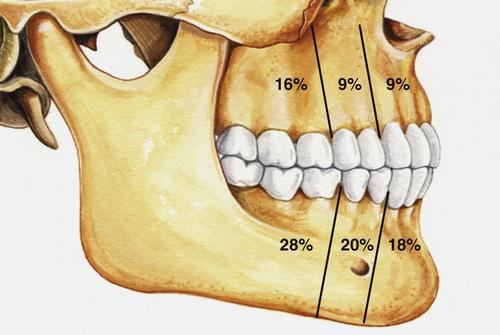

- most often involve mandibular third molars (65%)